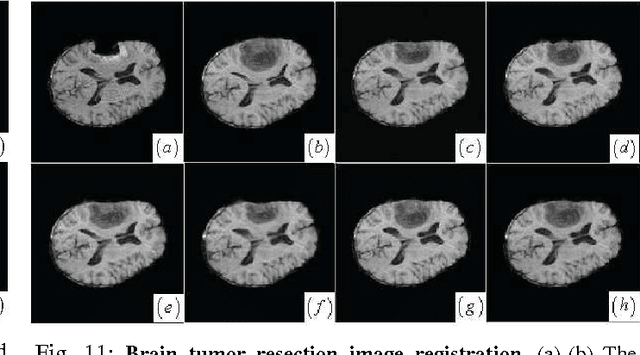

Abstract:For nonrigid image registration, matching the particular structures (or the outliers) that have missing correspondence and/or local large deformations, can be more difficult than matching the common structures with small deformations in the two images. Most existing works depend heavily on the outlier segmentation to remove the outlier effect in the registration. Moreover, these works do not handle simultaneously the missing correspondences and local large deformations. In this paper, we defined the nonrigid image registration as a local adaptive kernel regression which locally reconstruct the moving image's dense deformation vectors from the sparse deformation vectors in the multi-resolution block matching. The kernel function of the kernel regression adapts its shape and orientation to the reference image's structure to gather more deformation vector samples of the same structure for the iterative regression computation, whereby the moving image's local deformations could be compliant with the reference image's local structures. To estimate the local deformations around the outliers, we use joint saliency map that highlights the corresponding saliency structures (called Joint Saliency Structures, JSSs) in the two images to guide the dense deformation reconstruction by emphasizing those JSSs' sparse deformation vectors in the kernel regression. The experimental results demonstrate that by using local JSS adaptive kernel regression, the proposed method achieves almost the best performance in alignment of all challenging image pairs with outlier structures compared with other five state-of-the-art nonrigid registration algorithms.

Abstract:Joint saliency map (JSM) [1] was developed to assign high joint saliency values to the corresponding saliency structures (called Joint Saliency Structures, JSSs) but zero or low joint saliency values to the outliers (or mismatches) that are introduced by missing correspondence or local large deformations between the reference and moving images to be registered. JSM guides the local structure matching in nonrigid registration by emphasizing these JSSs' sparse deformation vectors in adaptive kernel regression of hierarchical sparse deformation vectors for iterative dense deformation reconstruction. By designing an effective superpixel-based local structure scale estimator to compute the reference structure's structure scale, we further propose to determine the scale (the width) of kernels in the adaptive kernel regression through combining the structure scales to JSM-based scales of mismatch between the local saliency structures. Therefore, we can adaptively select the sample size of sparse deformation vectors to reconstruct the dense deformation vectors for accurately matching the every local structures in the two images. The experimental results demonstrate better accuracy of our method in aligning two images with missing correspondence and local large deformation than the state-of-the-art methods.